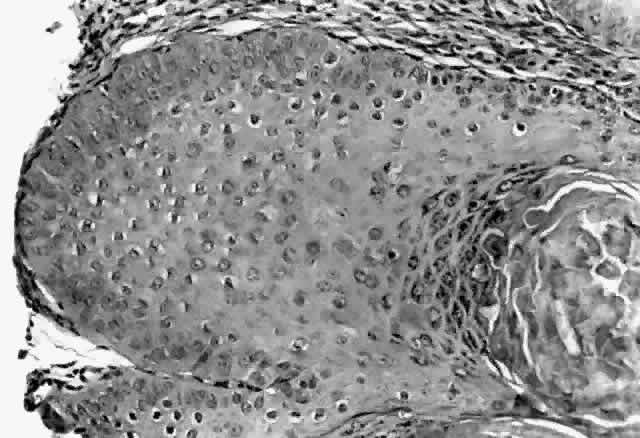

HPV-induced conjunctival squamous papillomas demonstrate papillomatosis, acanthosis, and koilocytosis (Fig. 6). Because they are mucous membrane lesions, those of the conjunctiva and lacrimal sac show no granular cell layer but will show keratinization if they are large or exposed (Fig. 7). In our experience the frequency of koilocytes is variable, even in lesions almost certain to be viral (Fig. 8). Scattered inflammatory cells may be present in the cores or epithelium. Virus can be detected immunohistochemically in the nuclei of the cells (Fig. 9).

Fig. 6. Eyelid papilloma, histology. High-power view of acanthotic epithelium and koilocytes. (Original magnification × 400)

Fig. 7. Immunohistochemical detection of human papillomavirus antigen. (Original magnification × 400)